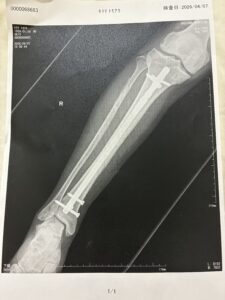

病院の先生に無理を言って4月末には退院できるように頼み⭕️がでました。

ゴールデンウィーク明けくらいから、教室の再開をしようと思ってます。

教室は家の2階にあるので松葉杖をつきながらゆっくり上がらないと、そして降りる時のほうが危ないですね。